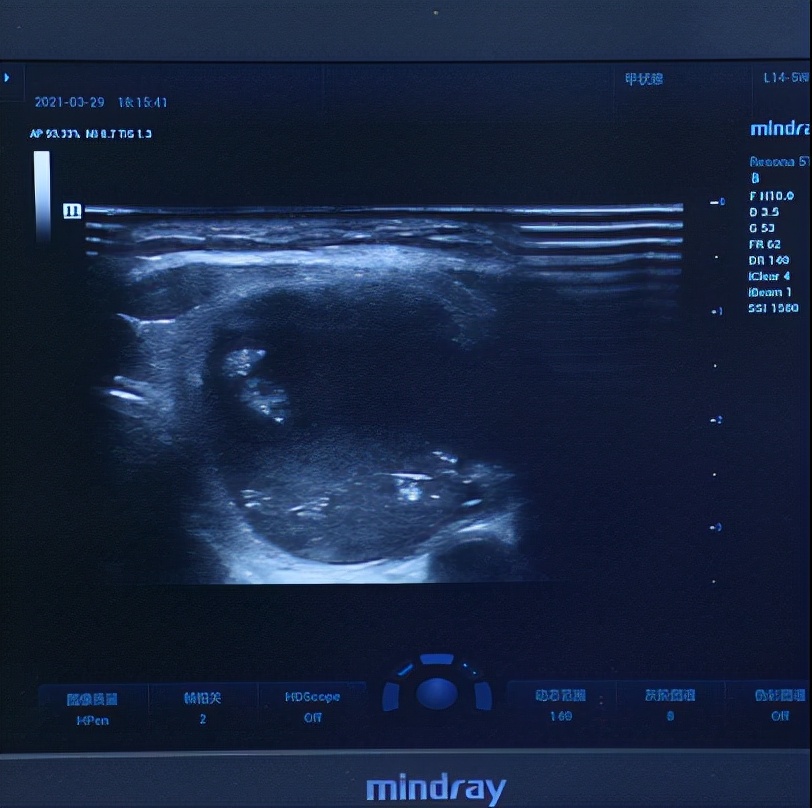

四维彩超出来,发现葛女士还有3mm的一个小结节,这个结节的评分很低,良性的可能性很大,我跟她说如果不想做手术可以先观察,等长大一点了做微创消融术也是可以的。